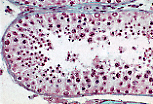

男性生殖系统